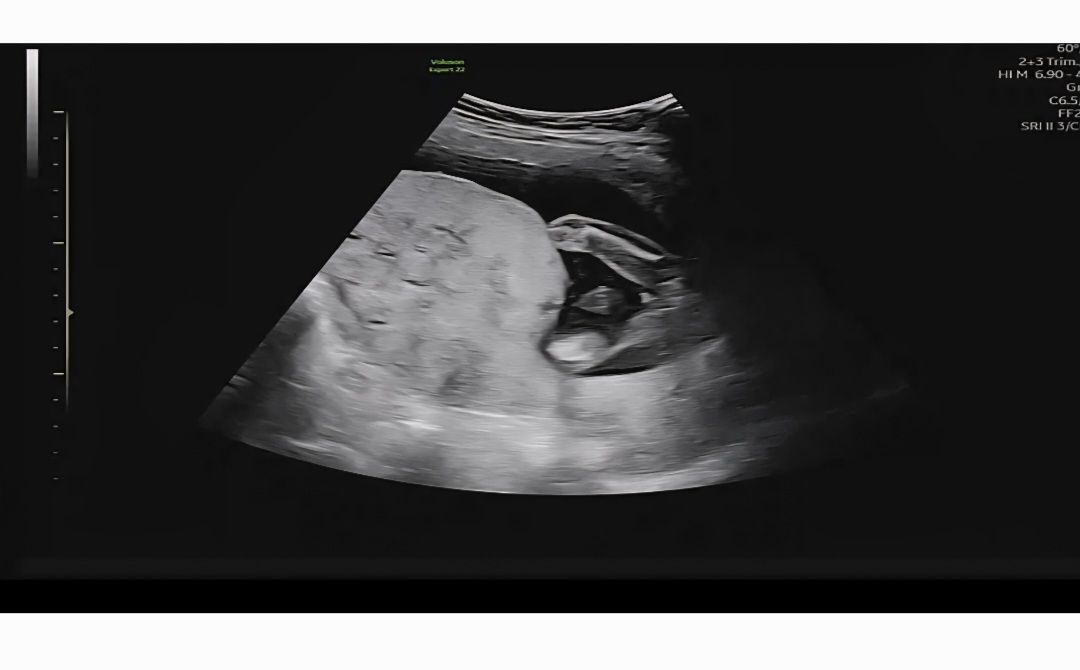

이정도면 딸이겠죠?

딸 확률이 높긴한데 정밀초음파때 다시 보자고 하셔서 궁금해요!

아들은 이렇게 확실하더라구요😂😂 딸 확정이신 듯 하네요!!

아들은 존재감 확실해요,,ㅎㅎ